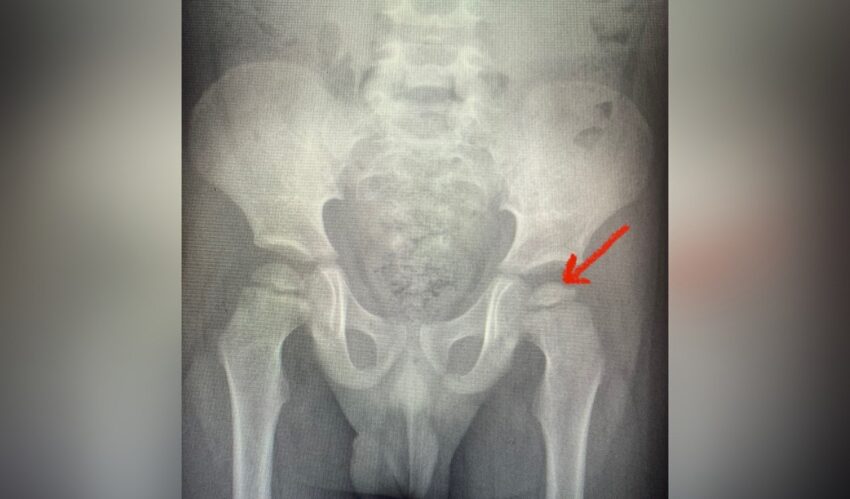

Медики Воронежской областной детской клинической больницы (ОДКБ) №2 при обследовании выявили у ребенка редкое заболевание — болезнь Пертеса, при которой наблюдается снижение высоты головки бедренной кости и потеря сферичности.